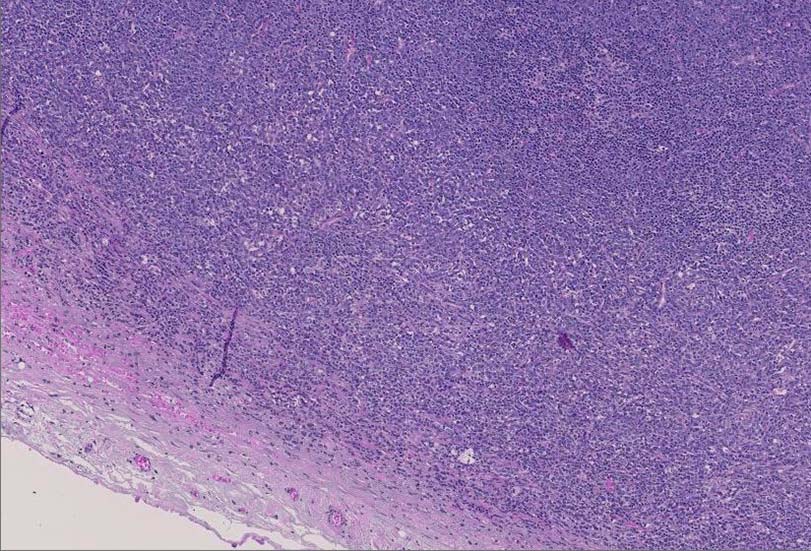

Myeloid sarcoma症例01: SPS223-Case05 Myeloid sarcoma

診断に難渋した顆粒球肉腫の1例 静岡赤十字病院 笠原正男: myeloid sarcomaのリンパ節病変.

腫大したリンパ節, 20x17mm. 萎縮した胚中心をもつ濾胞が散在する. 一見, Castleman病様の像. よく見ると, 線維化し軽度に肥厚した被膜下に小リンパ球の乏しい, 低倍で明るくみえる領域を視認できる.(サムネイル画像をクリックで大きな画像がみられます)

拡大像では, 類円形, 卵円形, non-cleaved nucleiをもつN/C比大の大きさのそろった細胞がシート状密に浸潤増殖している.

クロマチンは繊細で核は淡明, 核小体を1から数個もつ.